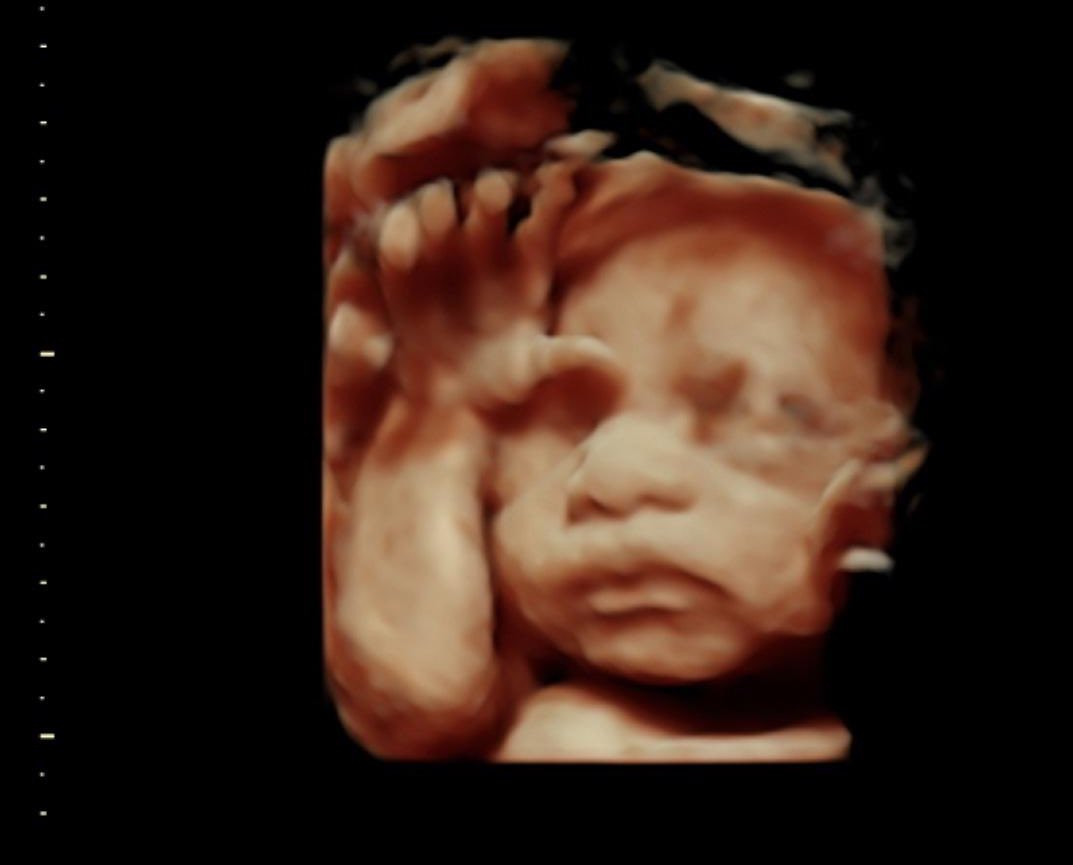

Can we all agree that it is a horrific evil to kill either of these babies?